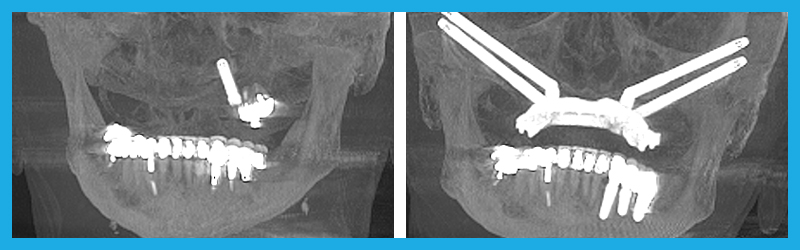

- Zygomatic and Pterygoid Implants: A Faster Solution: Traditional dental implant methods often require extensive bone grafting and a lengthy healing period, sometimes taking up to a year before final teeth are placed. Zygomatic and Pterygoid Implants bypass the need for bone grafts by anchoring the implants in the cheekbone and pterygoid plate, allowing for immediate loading of teeth. This not only shortens the treatment time dramatically but also provides a solution for patients who were previously told they weren’t candidates for implants due to severe bone loss.

Before and After

Zygomatic Implants